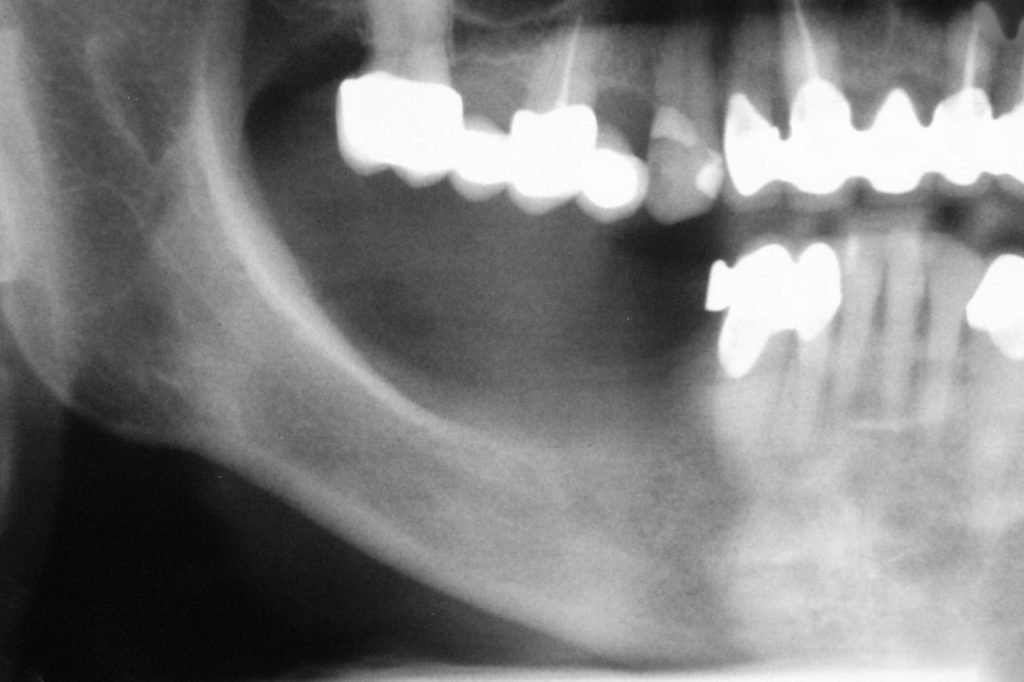

Przed podjęciem leczenia należy określić stopień zaniku kości szczęk oraz żuchwy. W tym celu przeprowadza się badanie kliniczne oraz odpowiednią diagnostykę obrazową pacjenta. Uwzględnia ona zdjęcie panoramiczne OPG jako podstawę dwuwymiarowego obrazowania podłoża kostnego oraz możliwe jest badanie tomograficzne CT lub bardziej precyzyjna tomografia stożkowa CBCT. Opcjonalnie wykorzystywana diagnostycznie tomografia pozwala na bardziej wnikliwą ocenę stopnia zaniku kości w trójwymiarowym, przestrzennym obrazie.